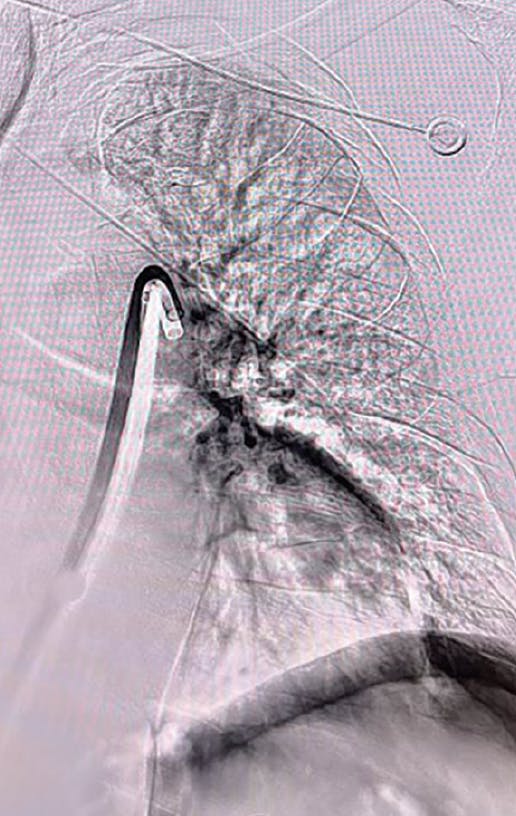

Figure 3. Post-thrombectomy lower right lobe angiogram.

Figure 4. Post-thrombectomy upper right lobe angiogram.

Figure 5. Post-thrombectomy left lobe angiogram.

Figure 3. Right post-thrombectomy angiogram.

Figure 4. Left post-thrombectomy angiogram.

Figure 3. Post-thrombectomy right and left angiograms.

Upon confirming vessel patency and thrombus removal with an angiogram (Figure 4, Figure 5, and Figure 6), right heart catheterization from the side port was performed, showing a significant drop in PA pressure from systolic 67 down to 49 mm Hg and excellent hemostasis. By the conclusion of the case, the patient no longer required supplemental oxygen, had no chest pain or shortness of breath, and experienced no significant bleeding. The patient was cleared for discharge the next day.

Figure 4. Post-thrombectomy right lobe angiogram.